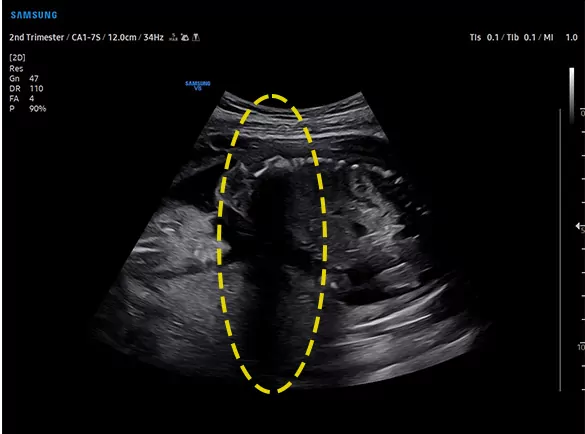

Покращуйте приховані структури в затінених областях

ShadowHDR™ вибірково застосовує високочастотний і низькочастотний ультразвук для виявлення тіньових областей, таких як голова плода або хребет, де відбувається затухання.